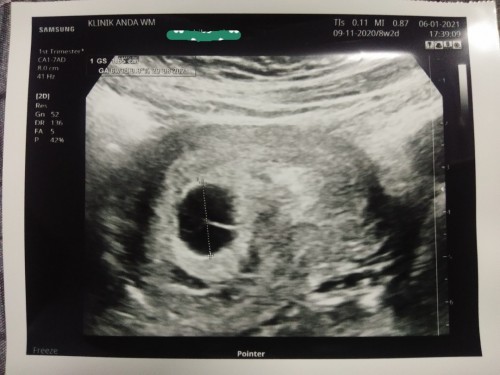

8 weeks 2 days

Normal ke kandungan dah 8 minggu 2 hari tapi nampak kantung je? ? Hari ni hari paling sedih sbb Dr. ckp get ready for miscarriages 😭. Tadi dh amik darah tapi keputusan kena tggu 48 jam. Xtahu nk ckp apa 😢. Tlg doakan saya dan baby sihat2 selalu ye.. Dr. ada ckp jgk last choice kne scan dari bawah 😪. Atau perlu ke saya pergi check kat klinik lain jgk???? #bantusharing #firstbaby #seriusnanya #pregnancy #mommybuntu #1stimemom

4 hari yang lalu saya pun buat scan. Kandungan 6 minggu 4 hari , scan kantung jE nampak besar , Dr cakap pun get ready for miscarriages sebab kantung nampak besar tapi tak nampak jantung, tapi Dr suruh saya jumpa lagi dlm 10 hari untuk check balik , saya doa kan semoga bayi kita baik2 saja amin